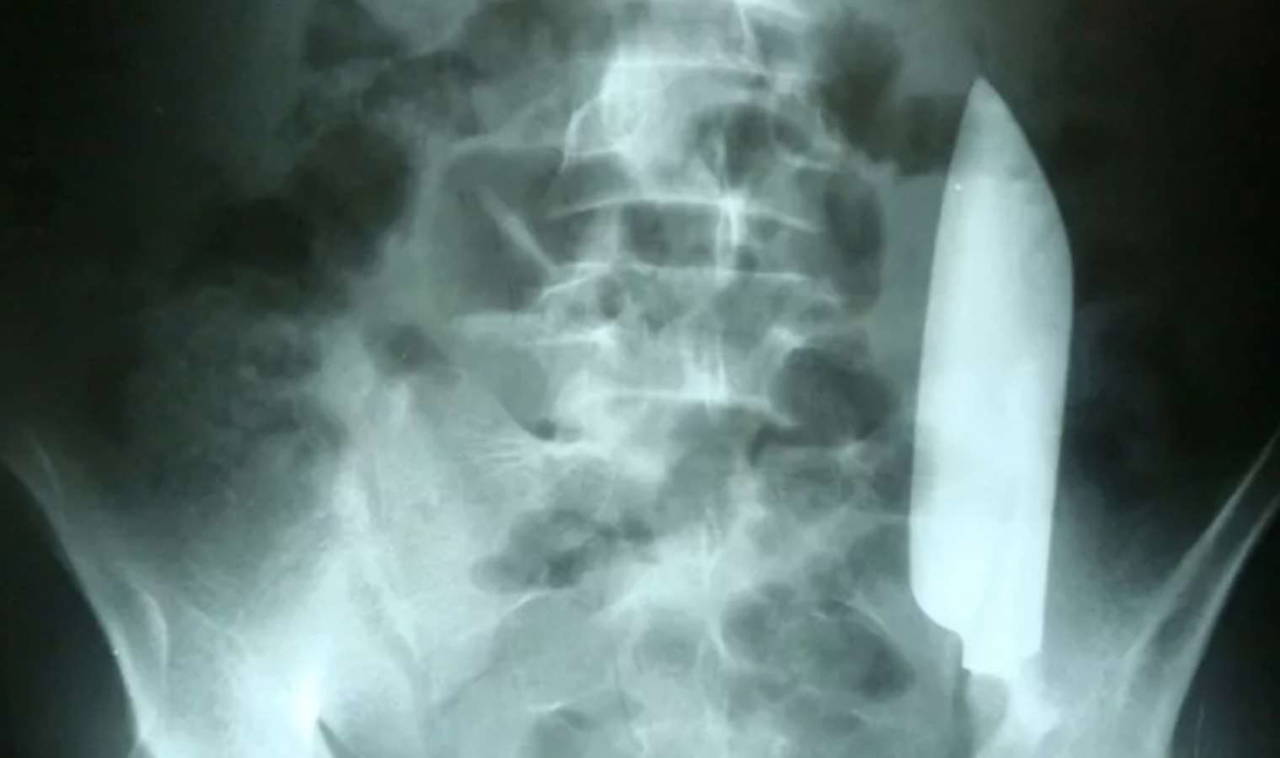

Yapılan röntgen sonucunda doktorlar, devasa bıçağın hala adamın içinde olduğunu ve şaşırtıcı bir şekilde hiçbir iç organa zarar vermeden karnının sağ tarafından sol tarafına doğru kaydığını tespit etti.

Bu olay, bıçağın sadece adamın içinde kalmamış olması değil, aynı zamanda olayın hemen ardından ek bir yaralanmaya neden olmaksızın karnında hareket etmiş olması bakımından olağanüstüdür.

Bıçak yarasının olduğu bölge göz önüne alındığında, adamın karaciğerindeki küçük bir yırtığın ilk bıçak darbesi sırasında oluştuğu düşünülmektedir.